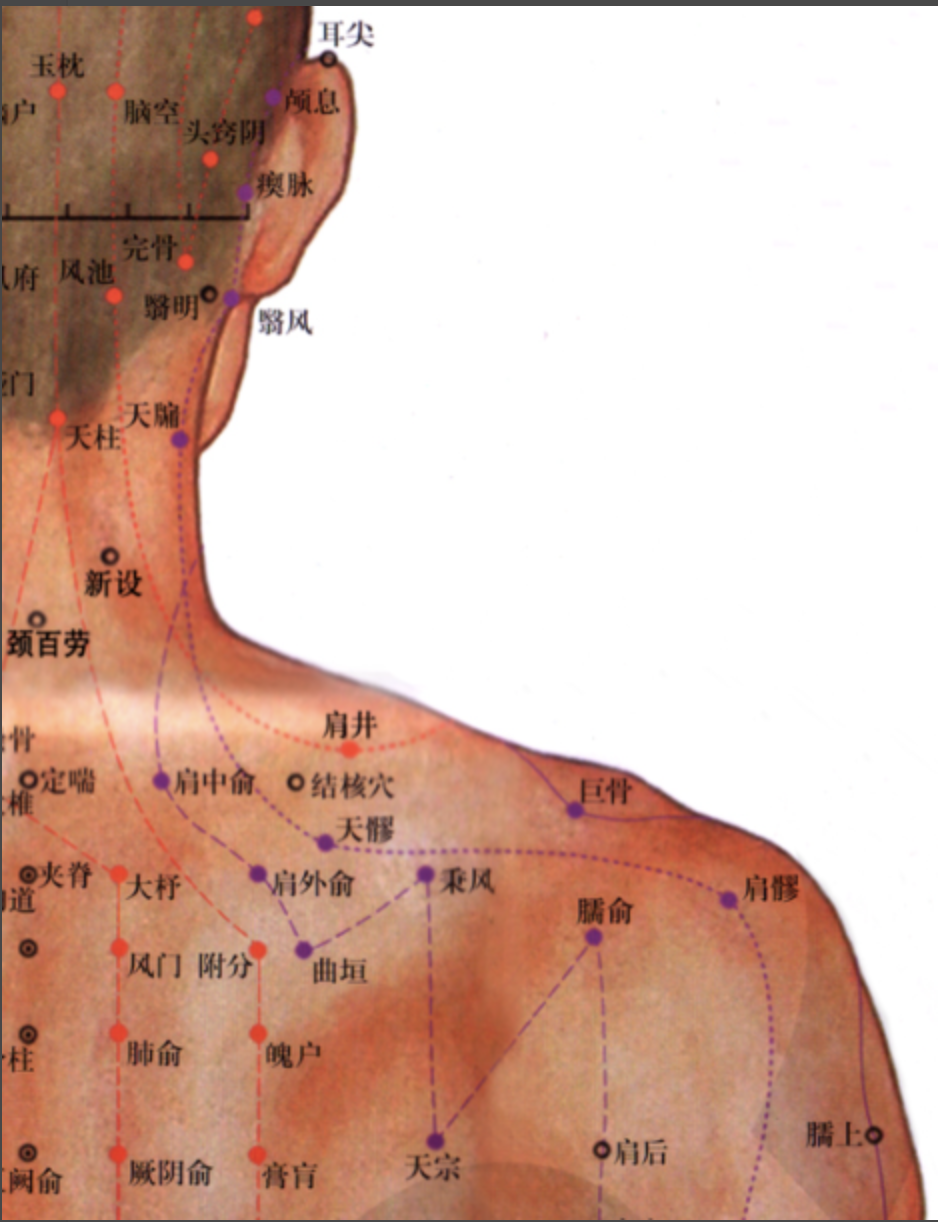

【(六)手太阳小肠经(图10-24-1)】

2、歌诀 手太阳经小肠穴,少则先行小指末,前谷后溪腕骨间,阳谷须同养老列,支正小海上肩贞,臑(nào)俞天宗秉风合,曲垣肩外复肩中,天窗循次上天容,此经穴数一十九,还有颧髎(liáo)入听宫。

3、经脉循行 起于手小指外侧端(少泽),沿手背外侧至腕部直上沿前臂外侧后缘,经尺骨鹰嘴与肱骨内上髁之间,出于肩关节,绕行肩胛部,交于大椎(督脉)向下入缺盆部联络心脏,沿食管过膈达胃,属于小肠。

缺盆部支脉:沿颈部上达面颊,至目外眦(zì),转入耳中(听宫)。

颊部支脉:上行目眶下,抵于鼻旁,至目内眦(睛明)、交于足太阳膀胱经。

4、主要病候 少腹痛、腰脊痛引睾丸、耳聋、目黄、颊肿、咽喉肿痛、肩臂外侧后缘痛等。

5、主治概要 主治头、项、耳、目、喉咽病、热病、神志病及经脉循行部位的其他病证。

天宗

【刺灸法】 直刺或斜刺 0.5 ~ 1 寸。

秉风

【刺灸法】 直刺或斜刺 0.5 ~ 2 寸。

【附注】 手三阳与足少阳经交会穴。